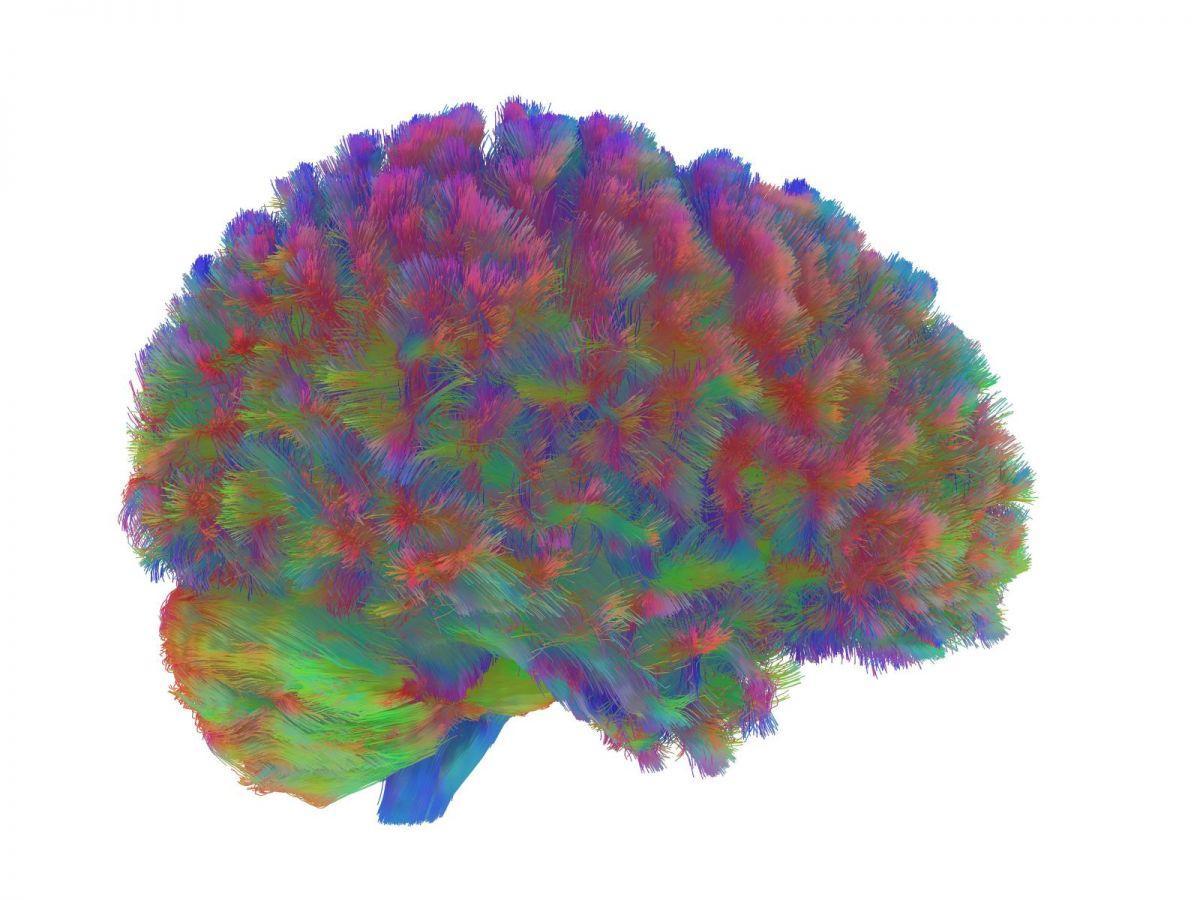

L’équipe a collecté les données d’imagerie à l’IRM des cerveaux de plus de 3.800 personnes et généré des cartes multicolores représentant les faisceaux de connexions entre les neurones constituant la substance blanche. Les images multicolores finales révélant ces voies neuronales sont issues de la technique du « fiber tracking ». « Notre objectif était de déterminer s’il existe des âges particuliers où le schéma de recâblage change et où une nouvelle phase commence. Pour ce faire, nous avons examiné l’organisation dans son ensemble plutôt que les propriétés individuelles, un peu comme si nous examinions une carte routière complète plutôt que des routes particulières », explique la chercheuse.